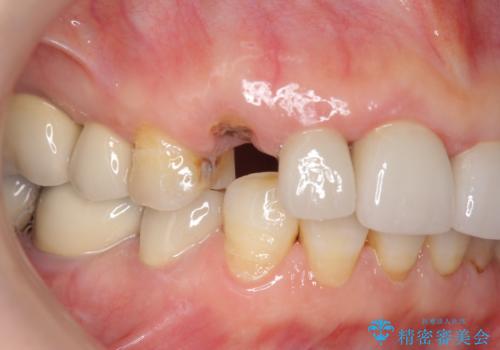

クラウン下に再発した深い虫歯 インプラントによる機能回復

- 定期検診で通院されていたところ、20年前に他院で治療した前歯のセラミック歯の下に深い虫歯が再発していることがわかりました。

ブリッジや歯の挺出を行い保存する提案も行いましたが、短期間の定期的な通院が難しくインプラントによる少ない回数での治療を希望されました。

前歯のインプラントを仕上げるには骨や歯ぐきの条件を整えることが肝要です。